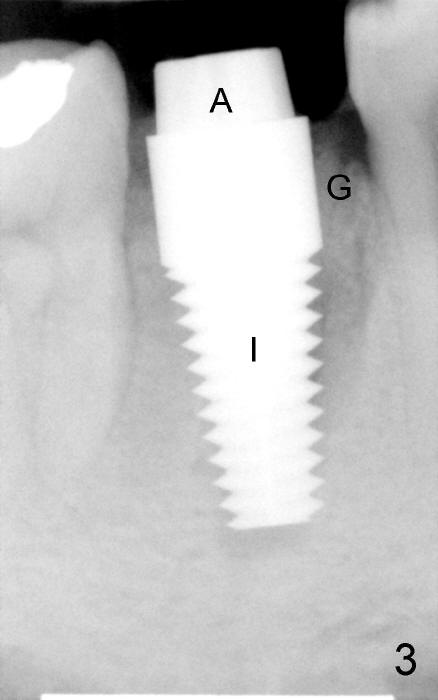

Due to the presence of the abutment (Fig.4 arrowheads), the perio dressing remains in place 7 days postop.